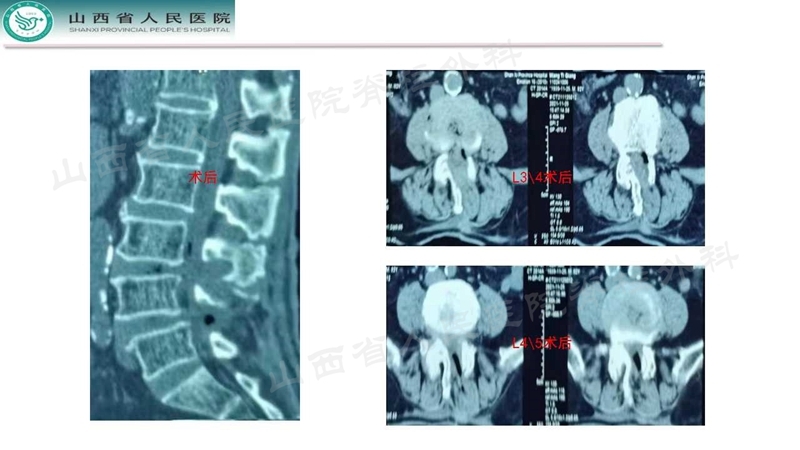

Case 2

Case 3